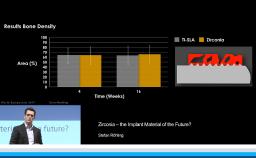

- describe the effect of different filling materials on the bone resorption